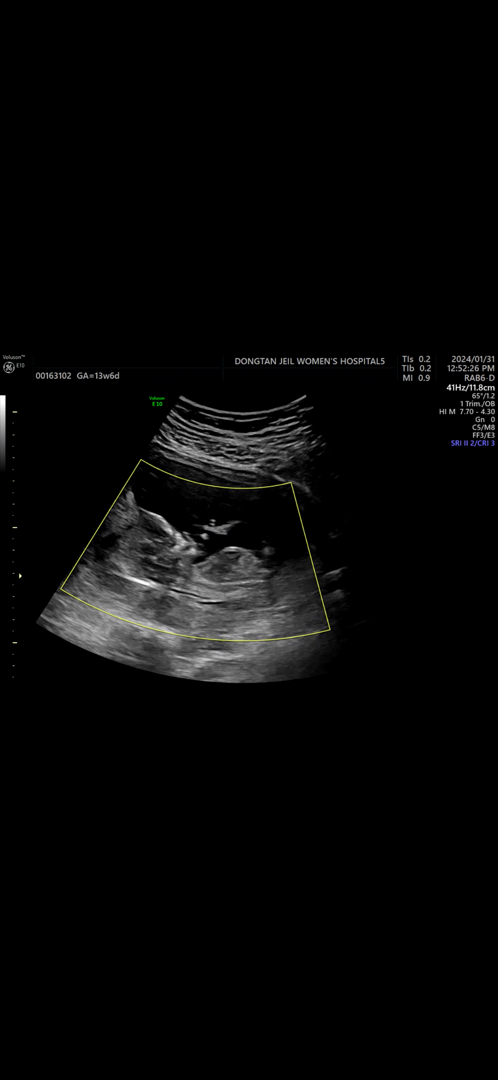

저도 각도법 한번만 봐주세용☺️

아들이던 딸이던 상관 없지만 4주 기다리려니 너무 궁금해서 !! 각도법 고수님들 저희 달떵이 한번 봐주세용